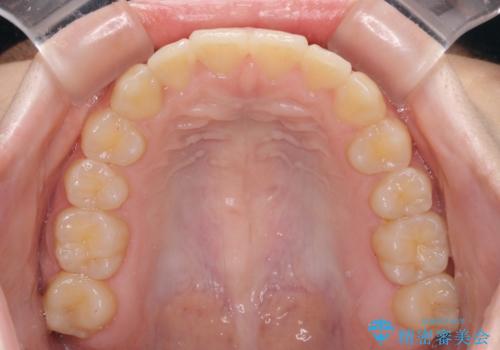

前歯のクロスバイト メタル装置での矯正治療

- 2年3ヶ月

当初は1年半程度の治療期間を想定していましたが、上下の正中を合わせていく過程で奥歯の咬みにくさが続いてしまい、2年以上の治療期間を要することとなりました。